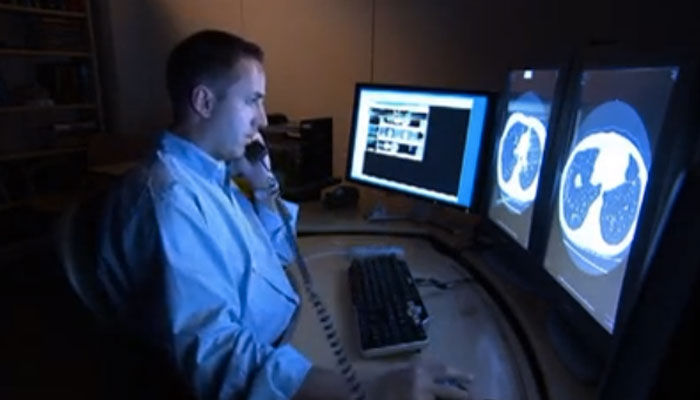

Comunicación post-examen